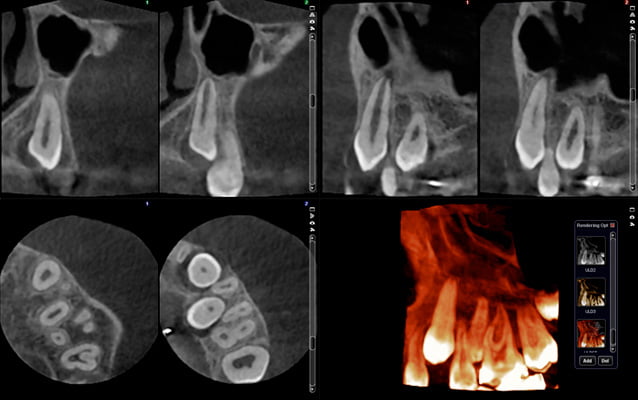

Normalna rozdzielczość

wielkość woksela 200 μm, dawka pacjenta ~86 μSv

Duża szczegółowość, średnia dawka

Normalna rozdzielczość przy ultraniskiej dawce

wielkość woksela 200 μm, dawka pacjenta ~20 μSv

Duża szczegółowość, niska dawka